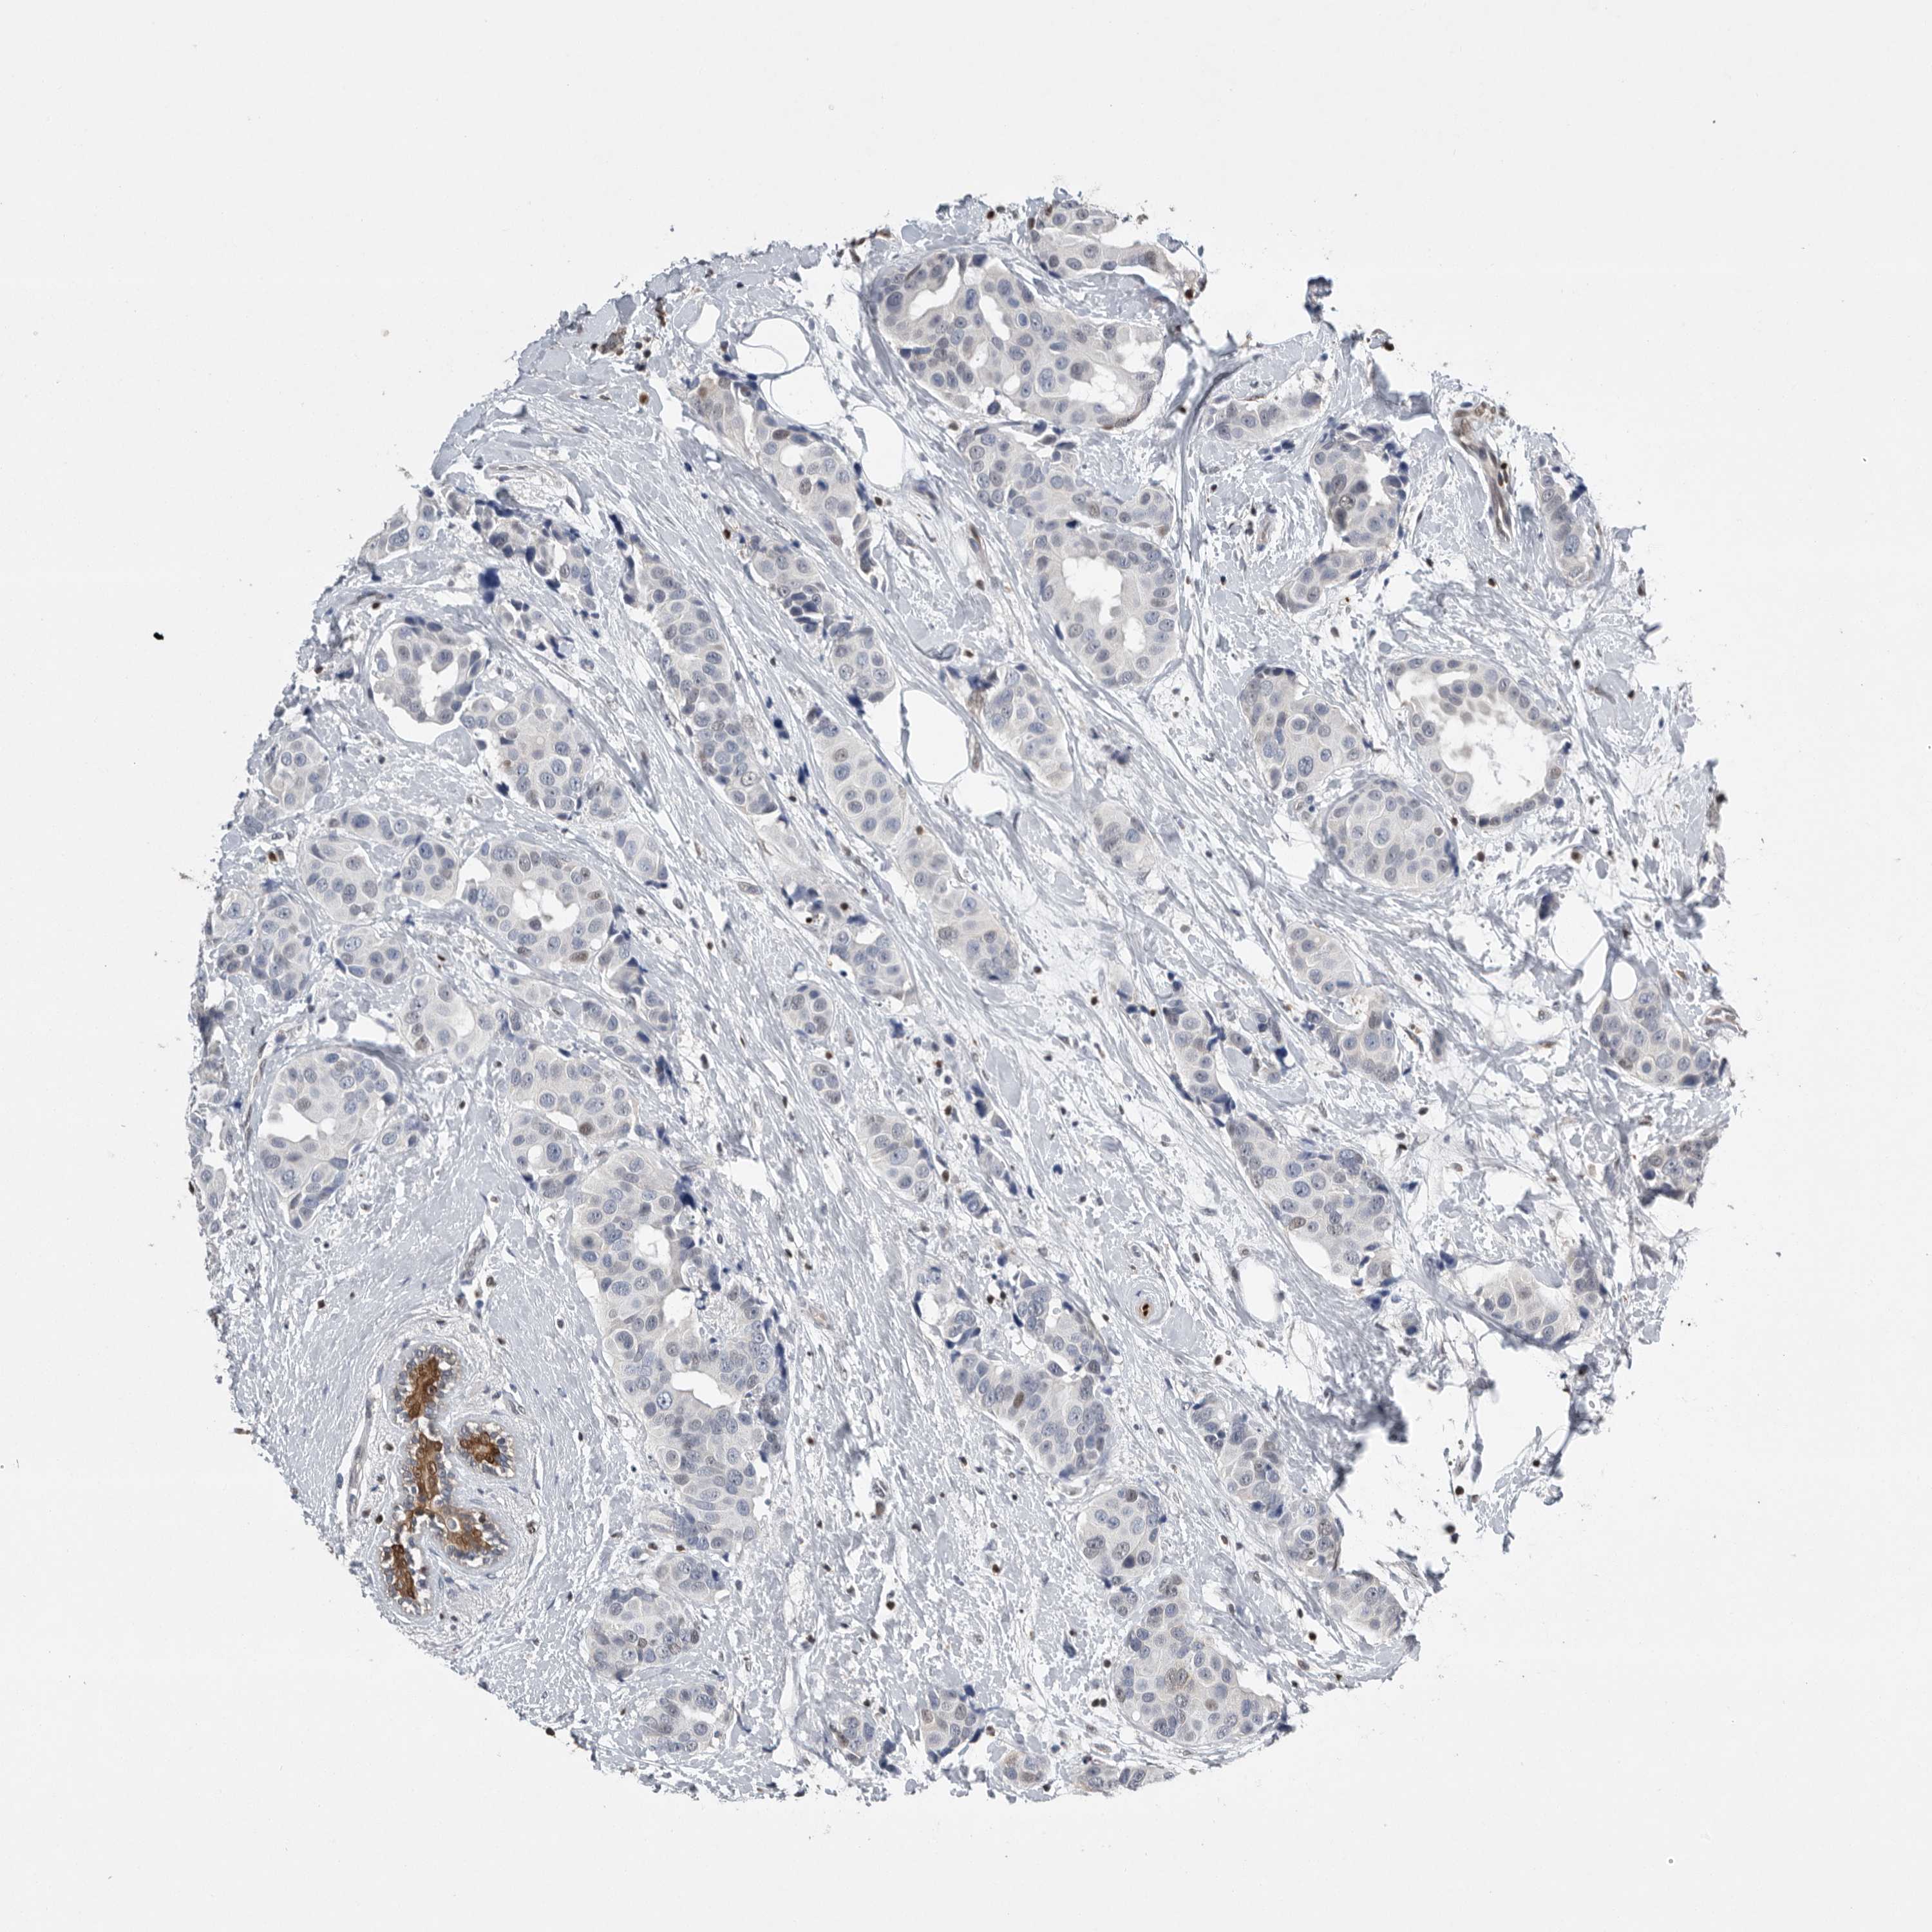

CANCER BREAST CANCER Show tissue menu

BRCA TCGA BRCA VALIDATION PROTEIN EXPRESSION